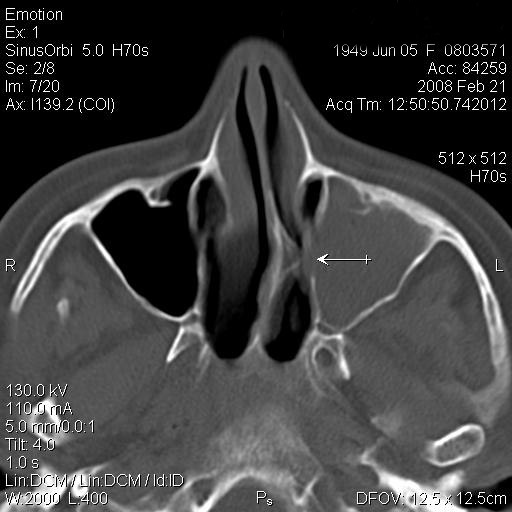

TC exostosis occipital congénica.

TC exostosis occipital congénita.